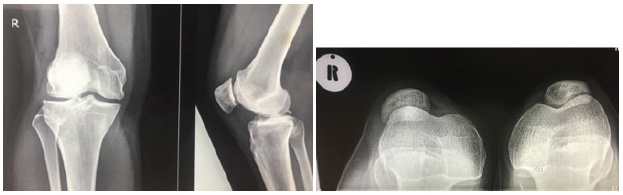

A 29 year-old teacher, presented with a history of recurrent instability of the right patella. The first episode occurred post fall during gym exercises and the patella shifted outwards. This was reduced by the gym instructor and she was subsequently put on a patella knee brace by the general practitioner. After removal of the brace she had multiple recurrent falls with the patella dislocating laterally and was unable to do exercises without a brace. Clinically there was effusion on the knee with positive grinding test. The ‘J sign’ was positive. X-rays showed laterally subluxed right patella as shown on the skyline view as shown in Figure 1. The TT -TG was 16mm with no trochlear dysplasia and with Insall Salvati ratio of 0.75 with normal alignment of the right lower limb. MRI revealed complete tear of MPFL (Figure 2). We therefore proceeded to do isolated MPFL reconstruction with Gracilis tendon autograft under spinal anaesthesia and tourniquet was inflated to 300mmHg for 115 minutes (See Figure 3). The average Blood pressure was 118/68 intraoperatively. The operation was uneventfully.

Figure 1: Pre-operative x -rays (Shows lateral sublimed right patella).